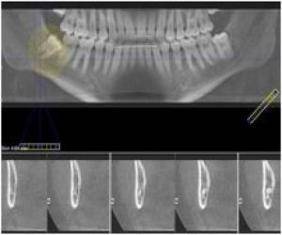

Une étude américaine souligne un risque accru de tumeurs bénignes au niveau du cerveau chez les personnes subissant régulièrement des radios des dents, notamment pendant leur enfance. Selon cette étude publiée le Mardi 10/04/2012 dans la revue américaine Cancer, les patients ayant subi tous les ans un examen radiographique des dents étaient de 1,4 à 3 fois plus enclins à développer ce type de tumeur qu'un groupe témoin constitué de patients en bonne santé. Pour parvenir à ce résultat, l'équipe de chercheurs de l'université de Yale dirigée par Elizabeth Clay a interrogé plus de 1433 patients américains âgés de 20 à 79 ans soufrant d’un méningiome.

Les auteurs de l'étude en question recommandent d'accentuer la vigilance en matière d'utilisation des rayons X pour les dents, et de ne pas dépasser une radio tous les ans ou tous les deux ans pour les enfants, et tous les deux à trois ans pour les adultes.

Il est à noter que l'Association des dentistes américains conseille de faire un examen radiographique des dents tous les ans pour les enfants, tous les 18 mois pour les adolescents et tous les deux à trois ans pour les adultes.